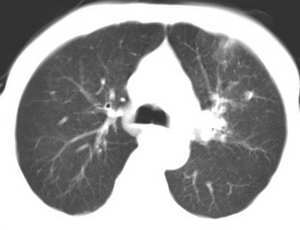

左肺上叶胸膜下不规则团块阴影,内见空泡,边缘光整,肺纵比率>50%,支持左肺癌的诊断。

左上肺病灶与胸膜脂肪线存在,未见明显胸膜凹陷征,虽然病灶边缘不规则,但未见明显“短毛剌、切迹征、免耳征、血管束集征”,其间亦见条索状、斑点状影,认为左上肺结核或炎性病变>周围型肺癌。

病灶比较虚 周围有明显渗出 卫星灶及条素影 病灶边缘有棘突 胸膜外脂肪层存在考虑结核

考虑肺结核可能性大。理由1.病灶形态不规则,其周有卫星灶,2.病灶没有毛刺征,灶周出现粗大索条影.